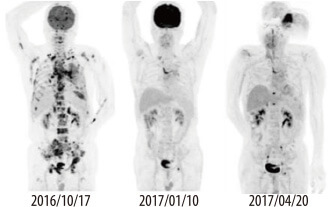

MoDEL™, QuarkBio’s Digital Liquid Biopsy Assay on DigiChip™, detects EGFR T790M drug-resistant mutation in patients with non-small cell lung adenocarcinoma for treatment guidance.

Patients with Lung Cancer Due to Exon 19 mutation in EGFR

- Exon 19 deletion was detected from patient’s tissue using qPCR

- Deletion was confirmed using patients’ blood sample using MoDEL™